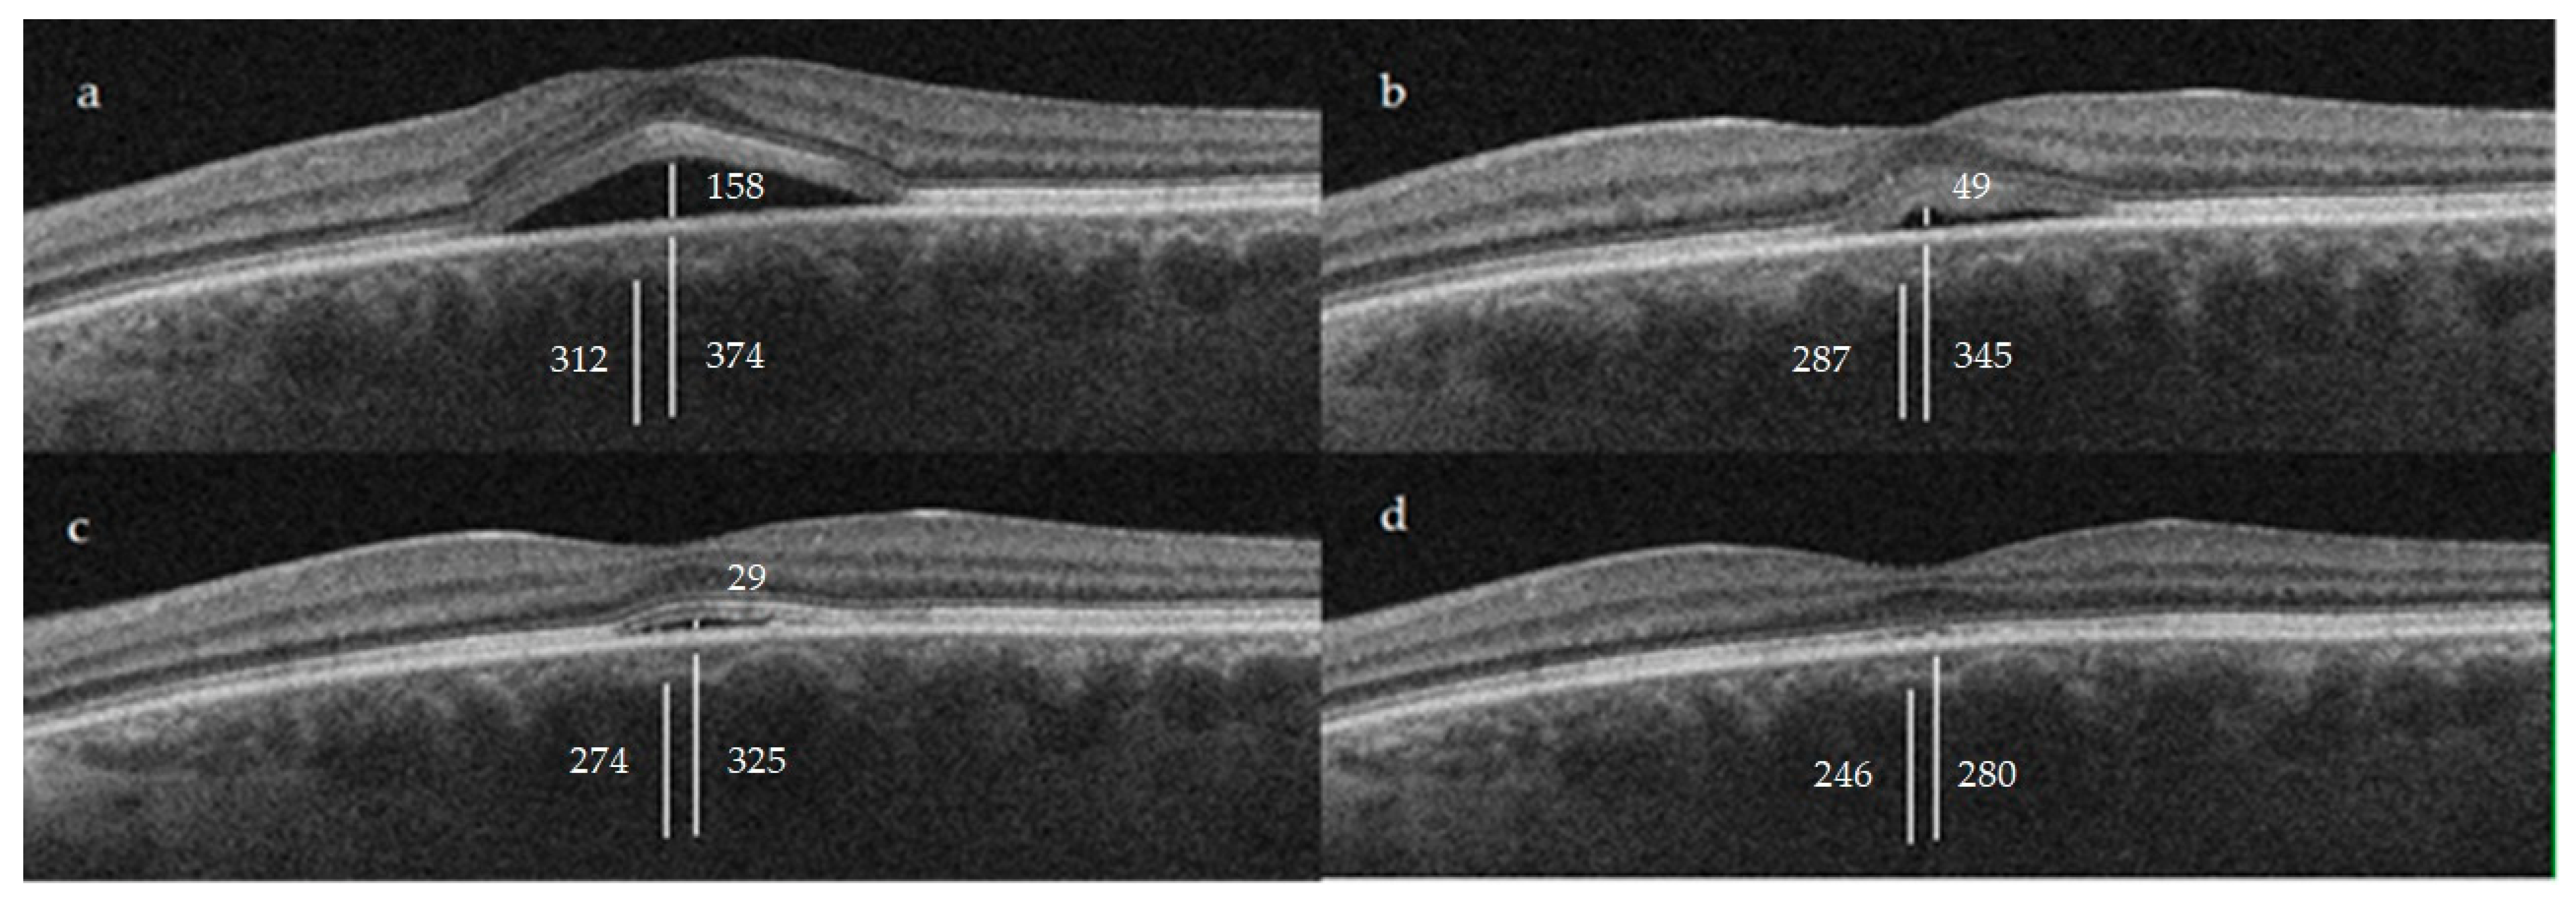

| CT | 374.9 ± 81.1 | 345.3 ± 71.5 | 0.0566 | 325.8 ± 59.2 | <0.05 | 280 ± 114.6 | <0.05 |

| Haller layer | 312.1 ± 71.3 | 287.4 ± 64.3 | 0.0953 | 274 ± 55.1 | <0.05 | 246 ± 115.9 | <0.05 |

| C-S | 62.8 ± 23.9 | 57.93 ± 20.8 | 0.3164 | 51.8 ± 18.3 | <0.05 | 34 ± 20.8 | <0.05 |